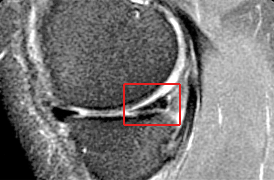

She presented to us with the MRI seen below. The red box on the MRI is over the medial meniscus cartilage. The MRI documents a chronic meniscus degenerative tear which had failed to respond to a partial meniscectomy. The options at this time when she presented to us were to repeat the meniscectomy. However, given the fact that it had already failed this did not seem to be a likely successful course of action. Therefore we planned to do a meniscus reconstruction where we would use a collagen scaffold as a regeneration template to regrow the missing meniscal tissue and therefore provide the shock absorber that her knee so clearly needed.

MRI (on right - a side view) revealed a tear of the posterior horn of the medial meniscus with inferior surface extension. MRI's are digital 'slices' through the body - this slice is from the side through the area of the meniscus at the back o the knee - the triangular bit in te red box is a cross section of the meniscus there - you can see that there is an interruption of the density of the structure.